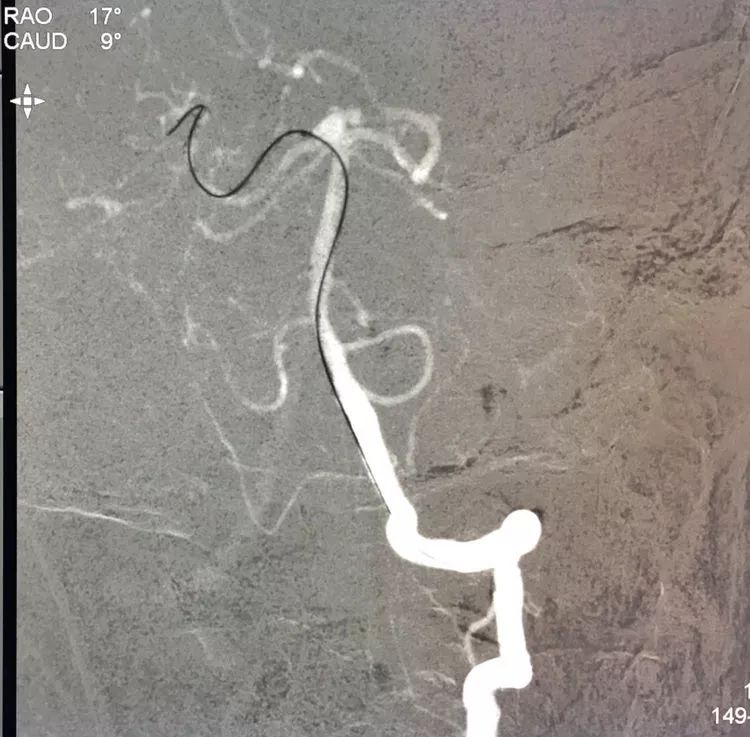

Sychro14微导丝携Headway21支架导管经左椎动脉-基底动脉进入右侧PCA,因瘤颈主要累及右侧PCA,故计划支架跨基底动脉顶端动脉瘤释放于右侧PCA-基底动脉内。

Echelon10(直头)微导管用Sychro14微导丝引入瘤腔内。

先送入一段弹簧圈

将LVIS支架(3.5×15)跨瘤颈释放于右侧PCA-基底动脉内

在支架保护下输送弹簧圈栓塞瘤腔

此时从工作位(右斜17°反汤9°)看弹簧圈分布致密,微导管头已被顶到瘤颈处

工作位造影看动脉瘤栓塞满意,子瘤已不显影,是不是可以收手了呢?

旋转增强器透视观察各个投照角度弹簧圈的分布情况,侧位透视发现瘤腔后部的弹簧圈分布疏松,形成死腔,看来革命还未成功,同志尚需努力呀!

回头再观察左椎动脉造影的三维成像,发现瘤腔确实有向后方突出的分叶,明确弹簧圈团后部的空虚处仍是瘤腔的一部分

此刻微导管的管头被支架压在瘤腔前部,显然无法再深入到瘤腔后部的死腔,这根直头的微导管该结束使命了,

换用一根新的Echelon10微导管,头端塑成C型,以Arvigo14微导丝引导(先前的Sychro14微导丝的头端已经有损了),经LVIS支架内部接近瘤腔后部的死腔,但微导丝可以进入死腔,微导管头死活钻不进去,被LVIS支架的网丝挡住去路,怎么办?那就隔着渔网袜挠痒!

微导管头顶在支架网眼处,投送一枚1.5-2的小圈,一开始弹簧圈走行入载瘤动脉(支架)内,用扭具调整弹簧圈头端的行进方向,并随之微调微导管头的方向和张力,圈终于成功钻入死腔!

再投入一枚1.5-3的小圈

继续钻入一枚1.5-2的小圈

嗯,完美收官!

回到工作位造影,显示基底动脉顶端动脉瘤完全栓塞,基底动脉顶端四根血管畅通。